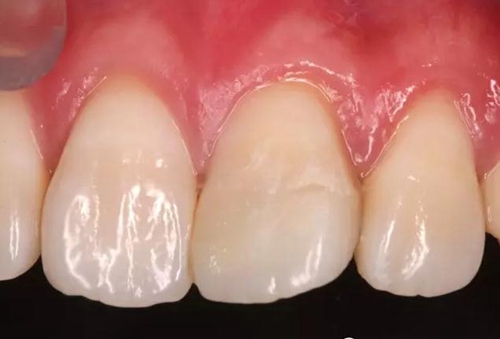

術(shù)后即刻口內(nèi)照

1個(gè)月后患者復(fù)診

口內(nèi)照顯示口腔衛(wèi)生狀況不佳,21牙面呈亞光狀態(tài),齦緣輕度紅腫。

給予健康教育,囑保持口腔衛(wèi)生。再次拋光。